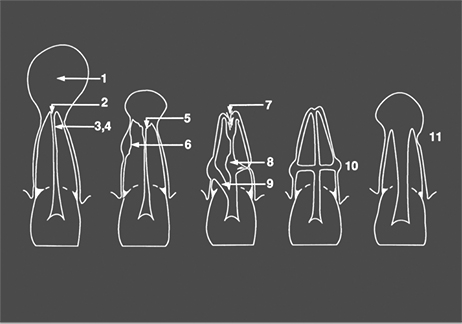

Pulpdent Paste, TempCanal and Multi-Cal are used in endocontics for all the following clinical situations outlined by Dr. G.S. Heithersay:

1. Exudation control; 2. Large periapical lesions; 3. Dressing; 4. Temporary root filling; 5. Apical inflammatory resorption; 6. Inflammatory resorption following trauma; 7. Apical internal resorption; 8. Internal-external root resorption; 9. Perforations; 10. Transverse root fractures; 11. Incompletely developed pulpless teeth

Heithersay GS. Calcium hydroxide in the treatment of pulpless teeth with associated pathology. J Brit Endo Society 1975;8(2):74-93.